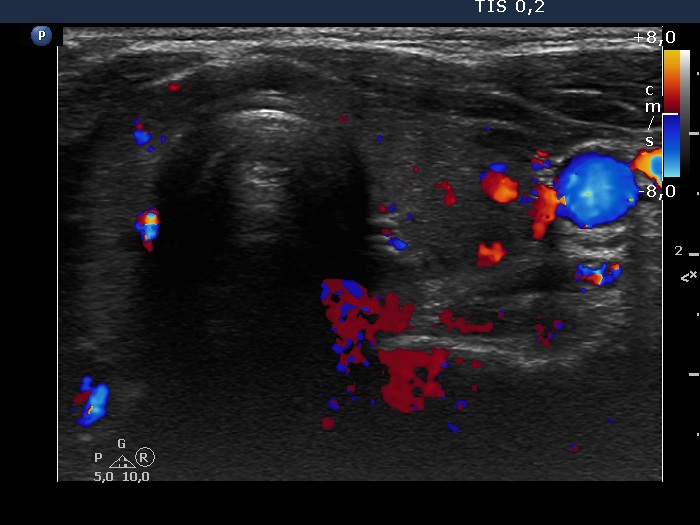

Left lobe, transverse scan, color Doppler mode. The vascularization is increased.